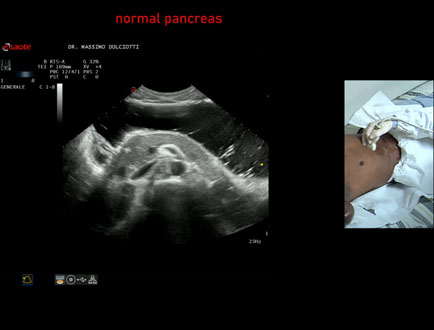

Data inserimento: 11/04/2025

Ecografia del: 26/03/2025

Strumento: Esaote MyLab Eight

Sonda: Convex Multifrequenza 1-8 MHz

Età Paziente: F 43 anni

Motivazione dell'esame: alvo alterno e pollachiuria.

Commento all'esame: le immagini ed il video documentano il pancreas, con regione cefalica, corpo e coda, ad ecostruttura e morfovolumetria regolare, di normale aspetto ipoecogeno.

Conclusioni: pancreas normale (normal pancreas).

Presentazione: Dr. Massimo Dolciotti - Ancona

Elaborazione digitale: Andrea Dini - Ancona